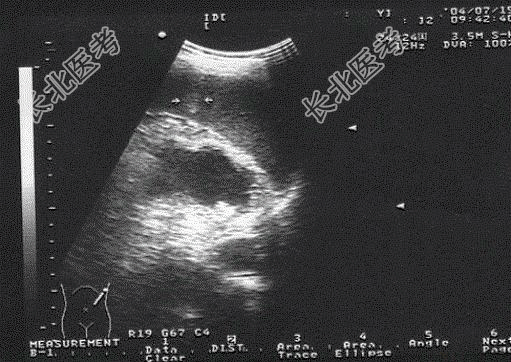

- [材料题] 男,25岁,例行体检时超声发现脾内占位。

- 简答题1、根据超声声像图诊断为?

- 简答题2、脾血管瘤治疗方法有?

- 简答题3、哪些因素会影响脾血管瘤的预后?